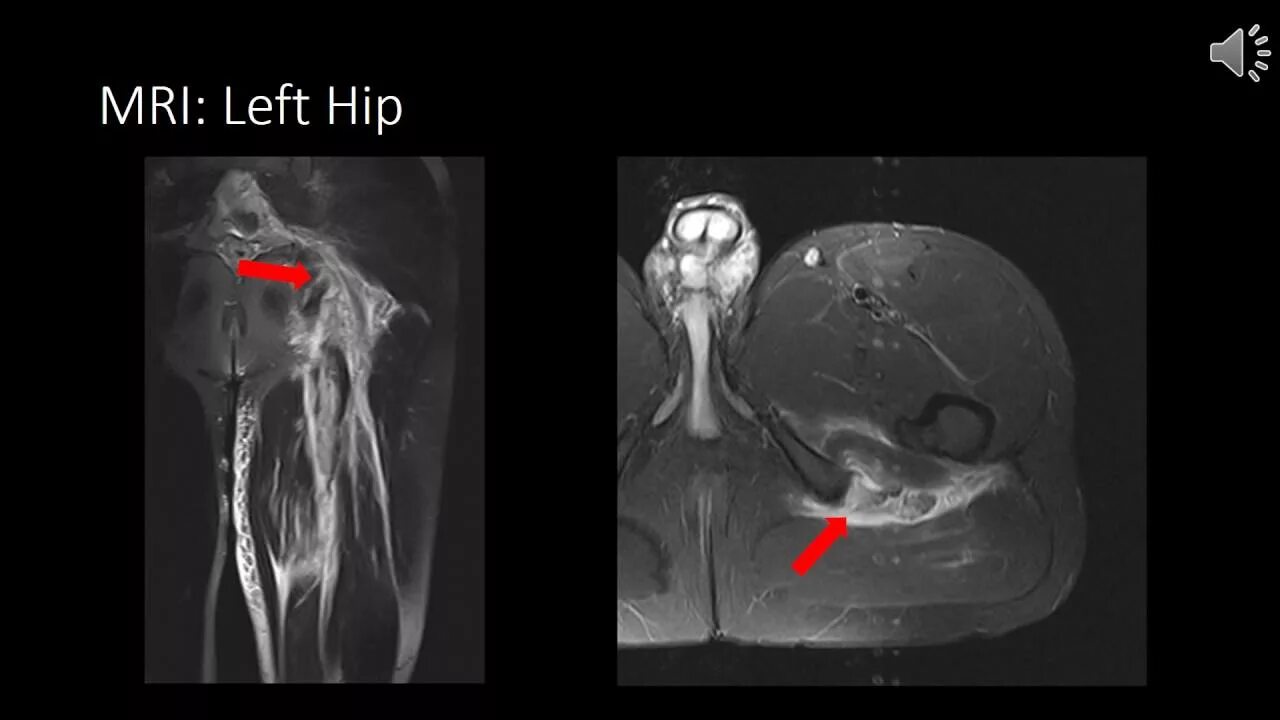

Хамстринг синдром тазобедренного сустава